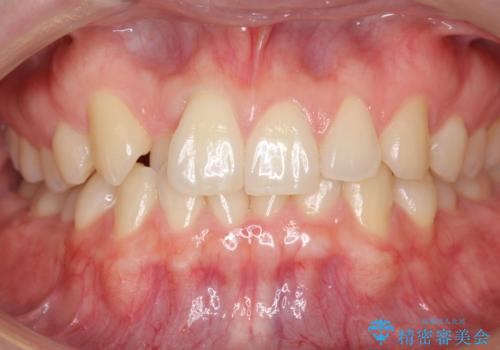

引っ込んだ前歯を並べる 歯を抜かないマウスピース矯正

- 右上の前歯が内側に入っているのを気にして来院。

右上の奥歯を後ろに移動して、前に出すスペースを確保してから並べました。

前歯が内側に入っていると、笑った時にそこが黒くなり、歯が抜けたように見えます。

口を開けたとき、笑顔の印象が大きく変わり、大変喜んでいただけました。